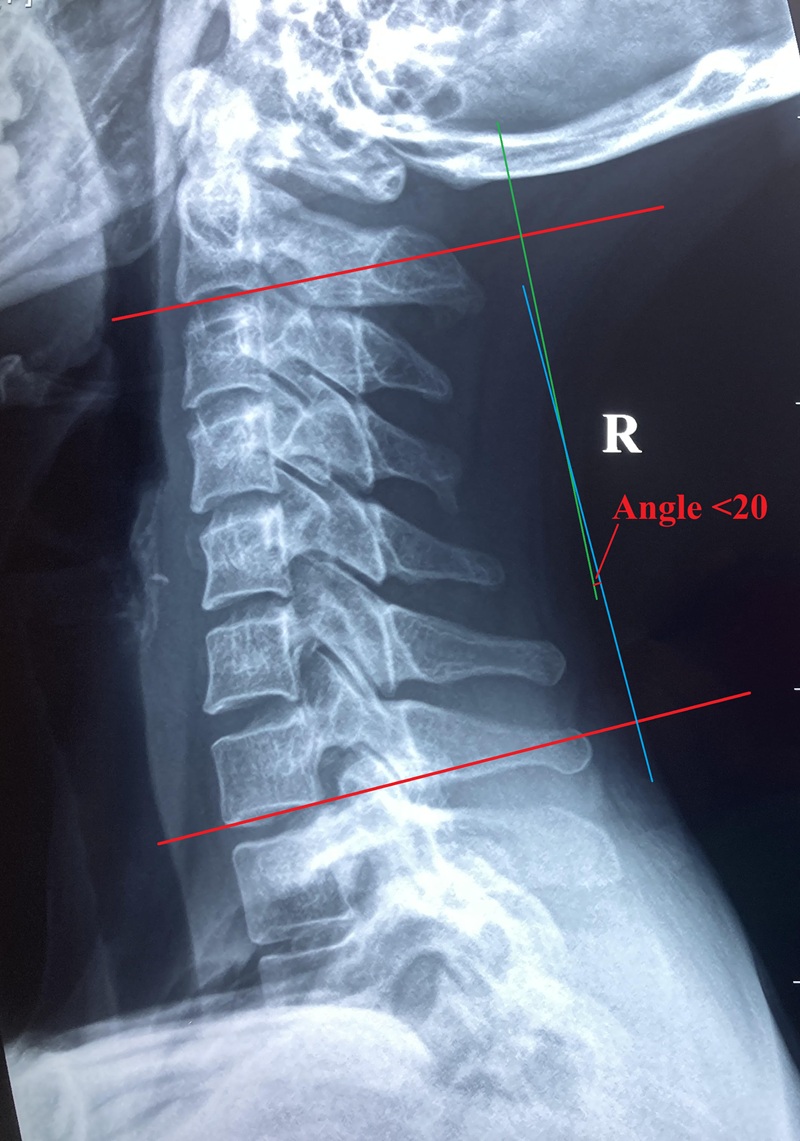

在功能方面,頸椎除支持頭部重量外,更負責協調頭部動作,配合頭部感官器官眼、耳、口、鼻感受環境變化及急機。致病原因如運動創傷或肌肉勞損都可以引起頸痛,寒背姿勢、工作壓力亦可促使頸痛發作。論病理發展,頸部肌肉、韌帶等軟組織傷患與頸椎關節疾患又可以互為因果引致痛症,嚴重者頸正常生理弧度拉直或反張。更甚者,長期頸痛往往伴隨抑郁等情緒病發作。

上頸椎病變可引致上頸椎神經根受壓或產生神經炎症,刺激枕大神經及枕小神經,導致後枕痛、頭側顳部或眉梭位置疼痛,甚或引發張力性頭痛。頸源性頭痛症狀包括頭後枕部牽拉感、頭皮刺痛,上頸椎有相應頸椎錯位或移位,X光張口位檢查亦可上頸椎表現旋轉、偏側或偏移等現象。(延伸閲讀頭痛篇章)